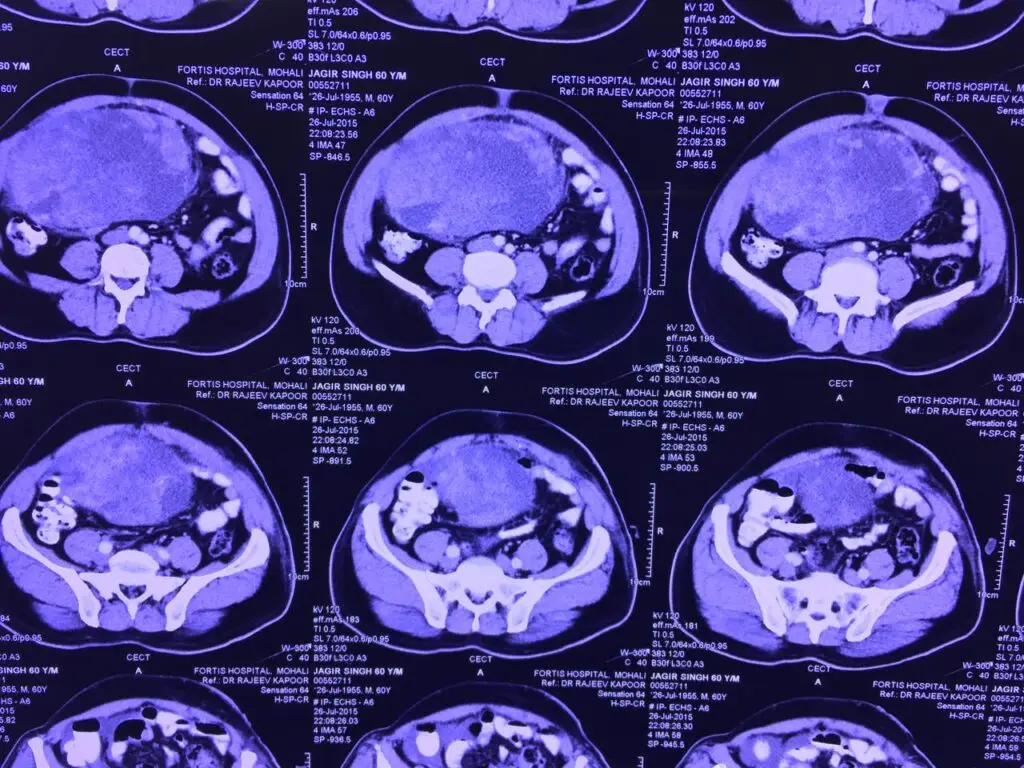

- MRI (Magnetic Resonance Imaging) is the preferred method for evaluating soft tissue tumors.

- CT scans are often used to assess deeper tumors, especially in the abdomen or chest.

- Imaging such as chest CT or PET scans helps determine if the cancer has spread (metastasized), most commonly to the lungs.